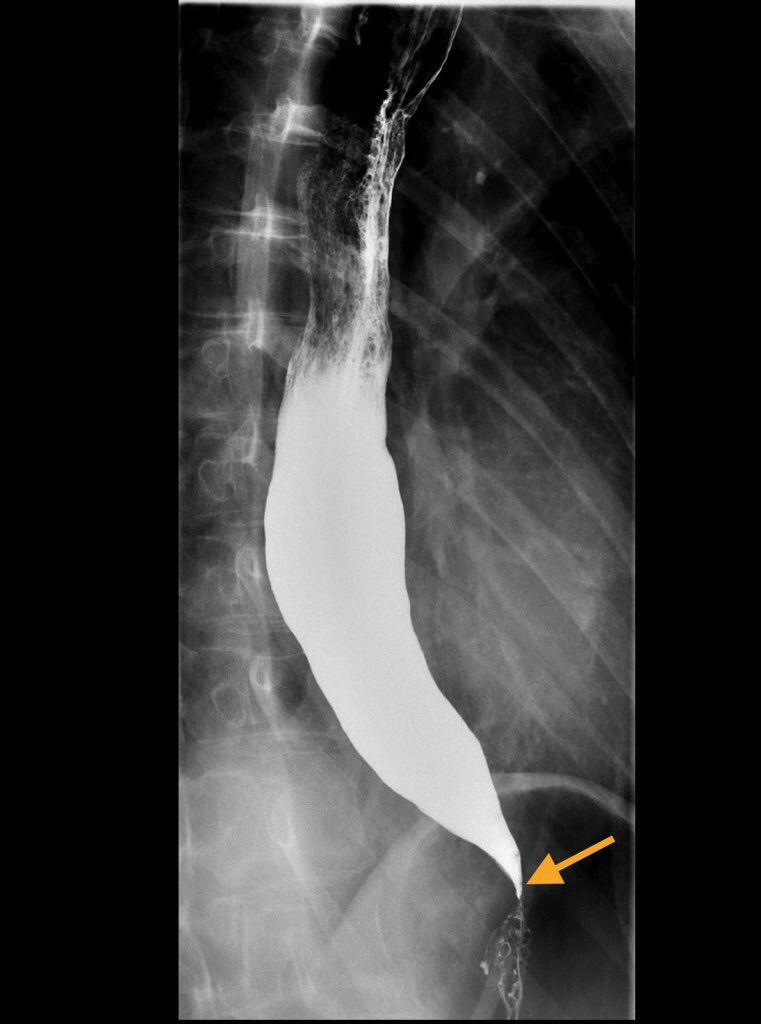

Achalasia is the inability of the lower esophageal sphincter (LES) to relax due to loss of myenteric plexus within lower esophagus. What is the most likely diagnosis? Look for: - Young patient, under 50 - Progressive dysphagia - No association with alcohol/tobacco Diagnostic test: - Barium esophagram will show a 'Bird's Beak' as esophagus comes down to a point. - Manometery is most accurate test. - CXR shows widening of esophagus but not a specific test. - Endoscopy is useful to exclude malignancy. Treatment: - Pneumatic dilation, effective in 80-85% of patients. - Surgical sectioning or Myotomy is most effective. - Botulinum toxin injection; but effects wear off in 3-6 months, require reinjection.